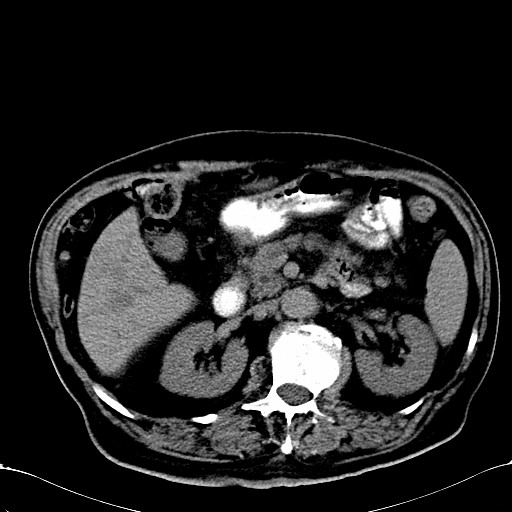

标题: CT28270:胰管扩张,肝多发占位 [打印本页]

标题: CT28270:胰管扩张,肝多发占位

患者,男,75岁。

肝脏多方低密度结节,边缘模糊,考虑多发转移,胰管明显扩张,建议增强扫描钩突情况

肝脏多发低密度灶,胰头似呈低密度,胰管扩张,建议增强,

胰管显著扩张,但胆总管未见扩张征象,不太符合胰头占位!考虑慢性胰腺炎.胃窦占位并肝内转移可能!mrcp胃镜增强一起上!